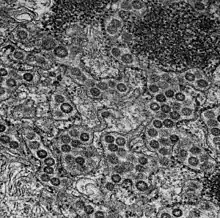

Cellule MRC-5

Les MRC-5 sont une lignée de cellules de type fibroblastes embryonnaires humains obtenue à partir d'un unique fœtus avorté en 1966 [1]. Elles sont utilisées pour réaliser des cultures de virus (par exemple le Cytomégalovirus), à des fins de diagnostic, de recherche ou pour produire des vaccins comme celui contre l'hépatite A[2]. Le fait que ces cellules descendent de cellules de fœtus avortés entraîne une controverse sur la vaccination[3].